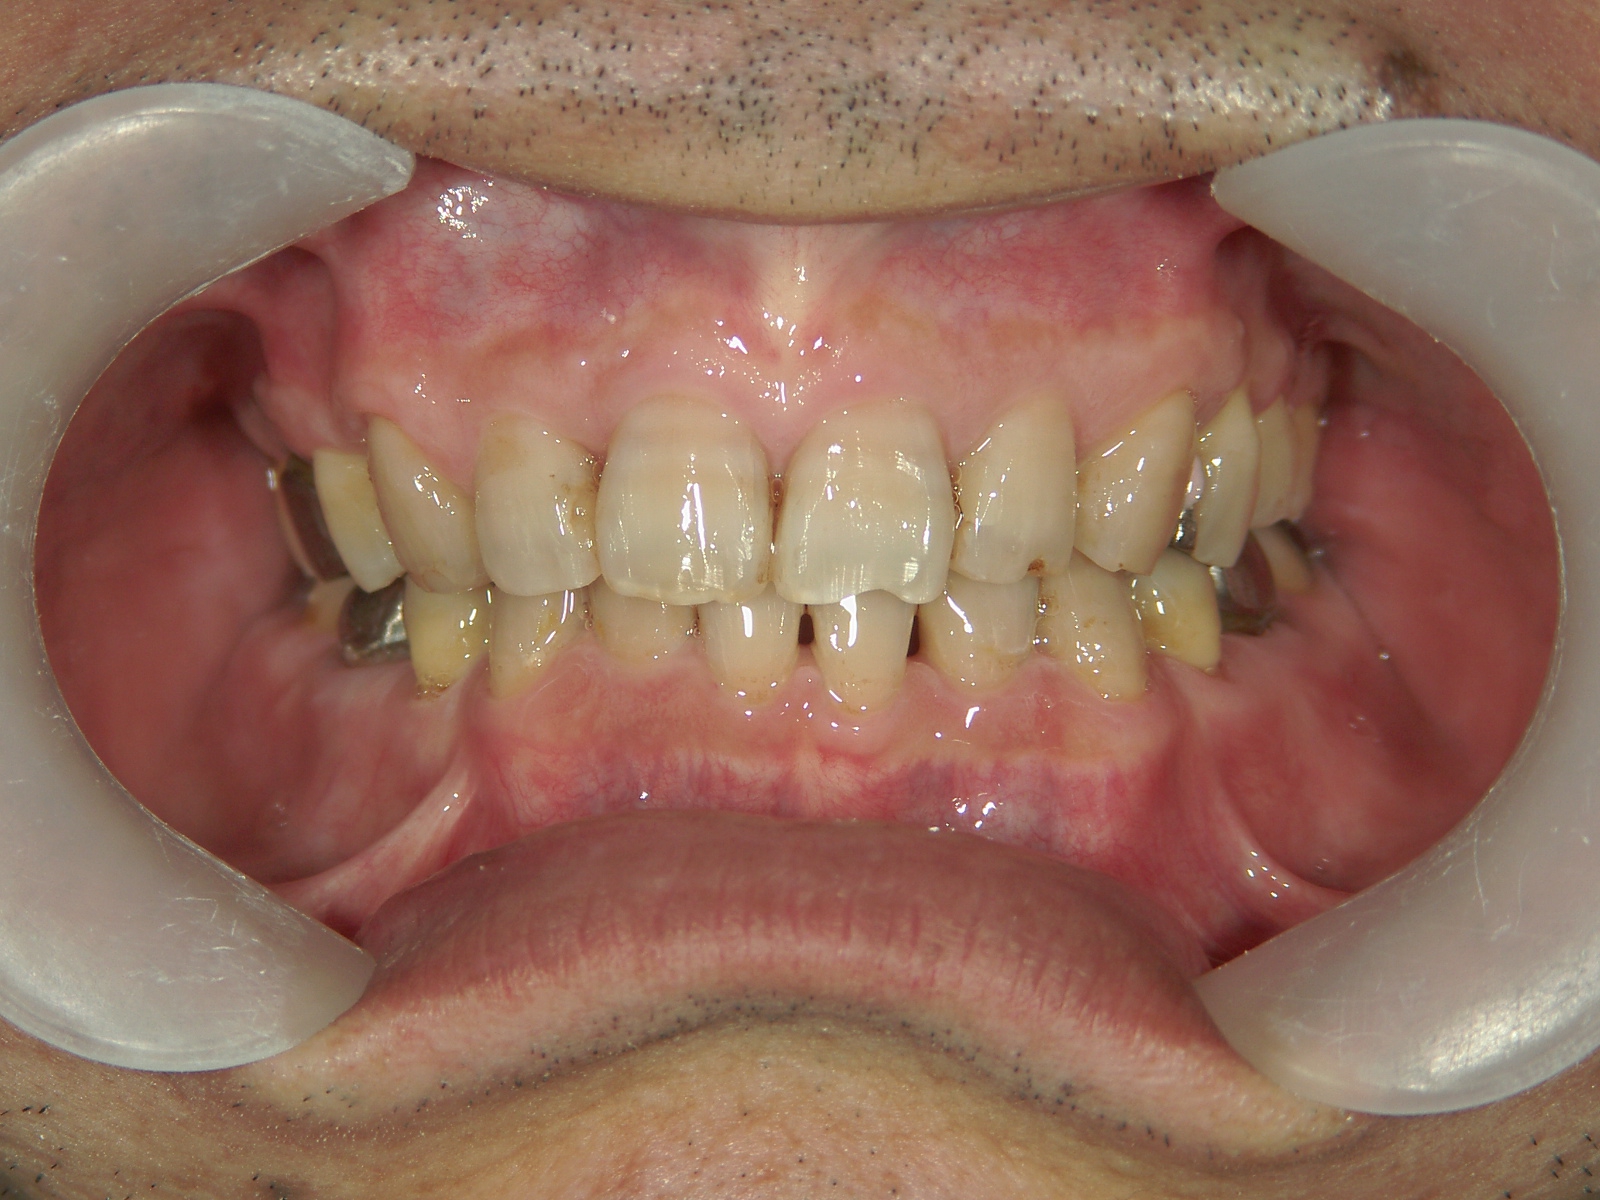

矯正歯科 治療前矯正歯科 治療前

矯正歯科 治療前 右上4番、左右下4番 計3本抜歯し、叢生を改善

no.22_8175_治療前_右.jpgno.22_8175_治療前_正面.jpgno.22_8175_治療前_左.jpg